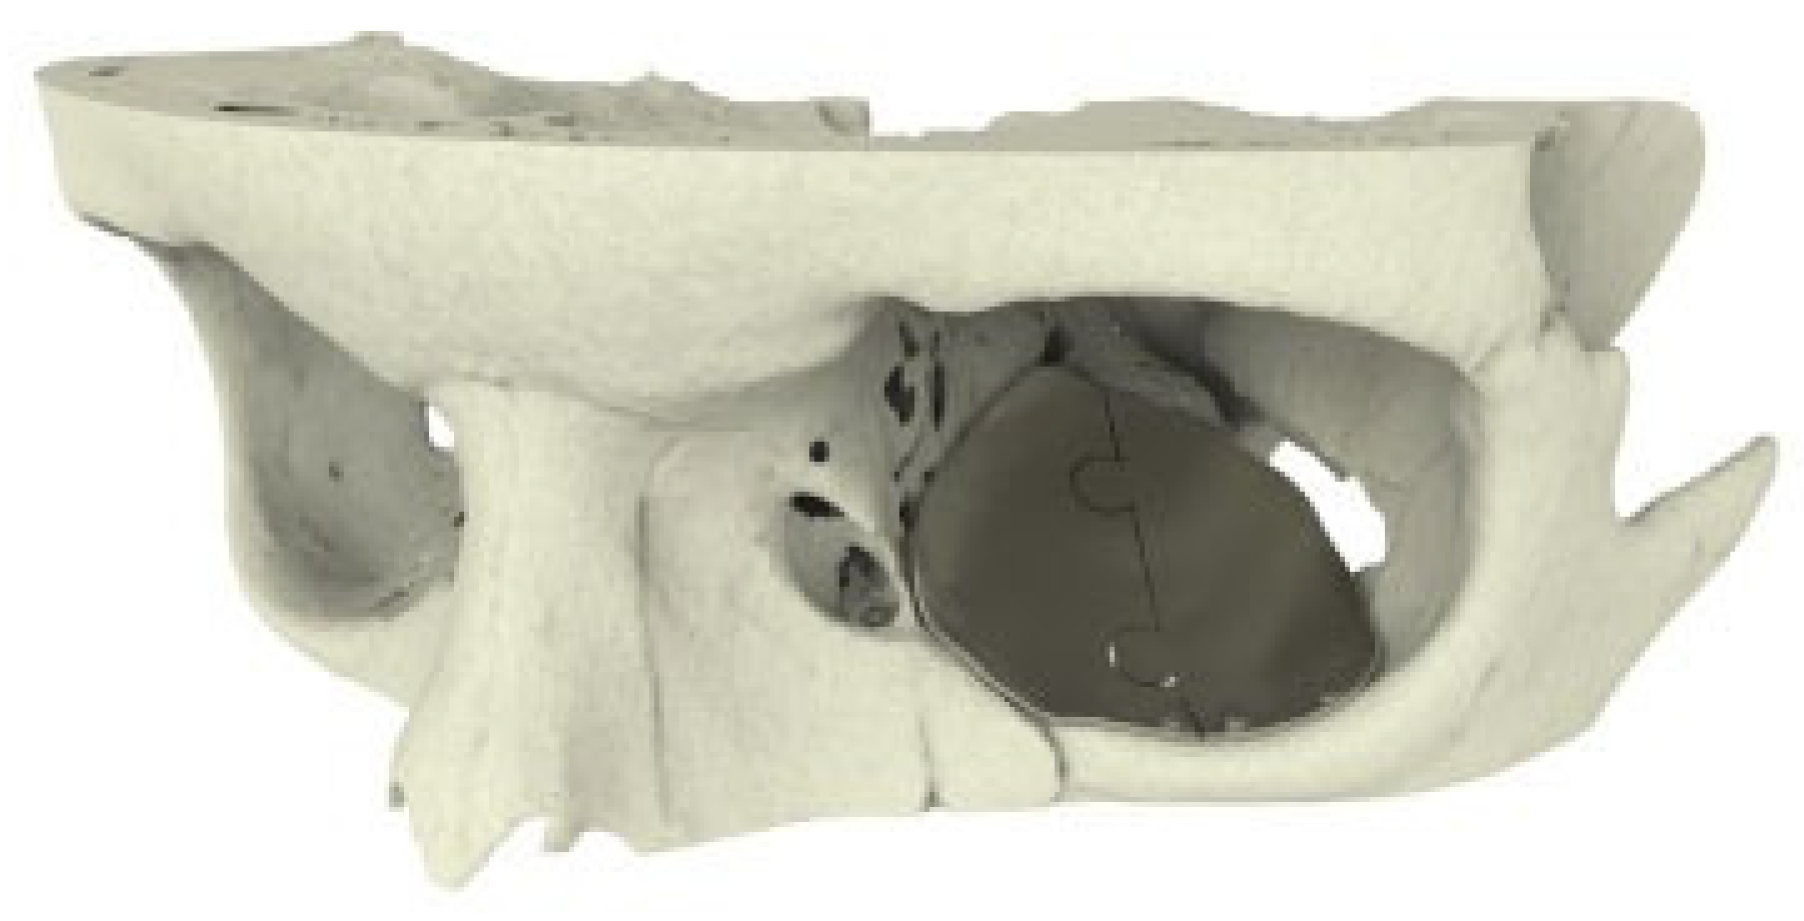

Figure 3. Case 1: Two-piece puzzle design (double tongue-in-groove).

A 12-year-old boy presented with a left orbital floor defect extending into the medial wall due to a traffic accident that occurred 1 month earlier. After rendering of the high-resolution CT DICOM data, mirroring was performed using Mimics Innovation Suite (Materialise, Heverlee, Belgium), which showed extension of the dislocation into the medial wall (►Figure 2). Two interlocking porous pieces were designed for transconjunctival insertion (►Figure 3). The surgery was performed 3 months after the accident. Screw position was determined after taking into account infraorbital nerve position and bone thickness. Microscrews (1.2-mm diameter; Surgi-Tec, Sint-Denijs-Westrem, Belgium) were used for plate fixation. The pieces did not overlap vertically, resulting in unfavorable rotational movement around the sagittal axis upon insertion (►Figure 4). Two months postoperatively, there was normal ocular motility, no enophthalmos, and no V2 disturbance.